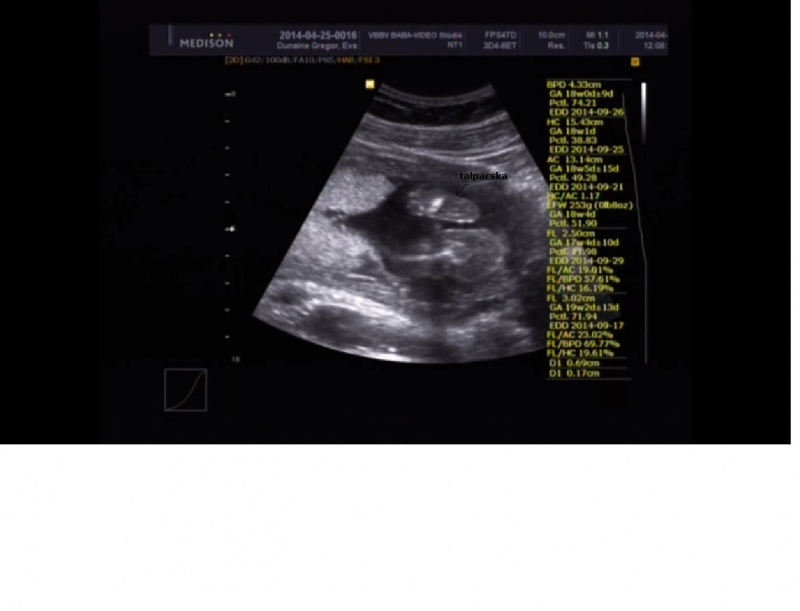

Terhességi kor menstruáció szerint 18 hét 4 nap, korrigált AFP: 1,14 MoM

BPD: 43 mm, fej átmérő)

HC: 154 mm,(fej körtérfogat)

AC: 131mm, (has körtérfogat)

FL:30 mm, (combcsont)

NB:6,9 mm(normál érték), Prenasalis rés:1,7 mm (normál érték). Jó életjelenségek, normál magzatmozgások, ritmusos szívműködés. FHR: 144/min. A biometriai adatok 18 hetes 5 napos graviditáshoz tartoznak.